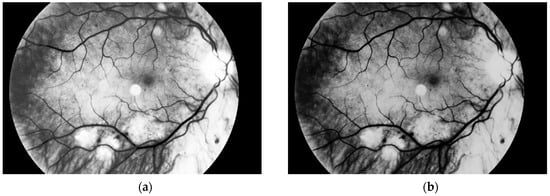

Another step, noise removal, is also done with median filtering. This algorithm is an efficient way to get precise results. Original image and images obtained after both of these steps are presented in Figure 10.

Figure 10. (a) Original image, (b) image after conversion to grayscale with green channel and (c) image after noise removal.